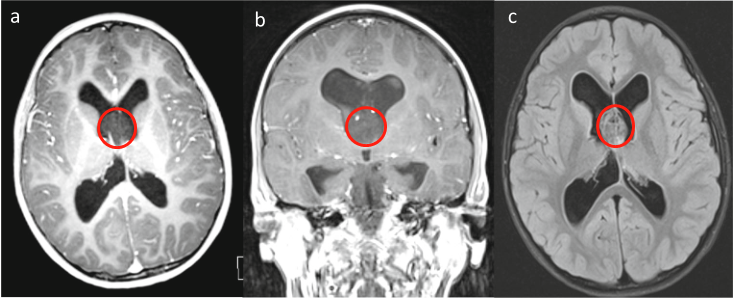

患儿欢欢近期三周持续出现头痛症状,除头痛外无其他明显不适表现。家属在症状持续存在的情况下,决定进行医学检查。磁共振检查结果显示大脑透明隔区域存在实质性肿块,伴有脑积水表现。

经诊断确认肿瘤属良性病变,生长速度缓慢。由于发现及时,预后评估较为乐观。治疗团队由德国Joachim K. Krauss教授主导,通过术中磁共振引导下右脑室经皮层入路实施肿瘤切除手术。

手术过程中发现肿瘤与穹隆结构粘连,未能实现完全切除,但达到最大程度安全切除。术后病理诊断为菊形团形成性胶质神经元肿瘤(RGNT),属于WHO Ⅰ级低级别肿瘤,具有较低复发风险。

术后随访显示患儿恢复良好,未出现新发神经系统症状,头痛症状完全缓解。术后两年随访显示病情稳定,脑积水改善,无肿瘤复发迹象。患儿无需接受放化疗辅助治疗,已恢复正常生活。